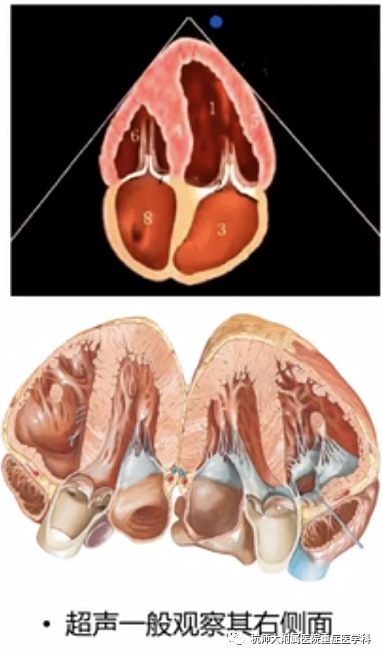

b.胸骨旁短轴切面:位置选择:胸骨左缘第2~5肋间,超声探头标记点指向左肩;操作过程中在获得胸骨旁左心室长轴平面后,将二尖瓣调整至屏幕中央,超声探头顺时针旋转约90°,使超声探头标记点朝向左肩可获得二尖瓣水平短轴切面。将超声探头尾部向心底倾斜,超声探头声束向心尖倾斜,可依次获得胸骨旁左心室短轴乳头肌平面和心尖平面。

什么是超声容积探头重症心脏超声图像的获取_https://www.jmylbn.com_新闻资讯_第15张什么是超声容积探头重症心脏超声图像的获取_https://www.jmylbn.com_新闻资讯_第16张

主要评估内容:(1)左心室收缩功能定性评估及分级;(2)左心室壁节段运动障碍;(3)右心形态改变;(4)室间隔运动评估;(5)评估室间隔缺损的最佳切面。